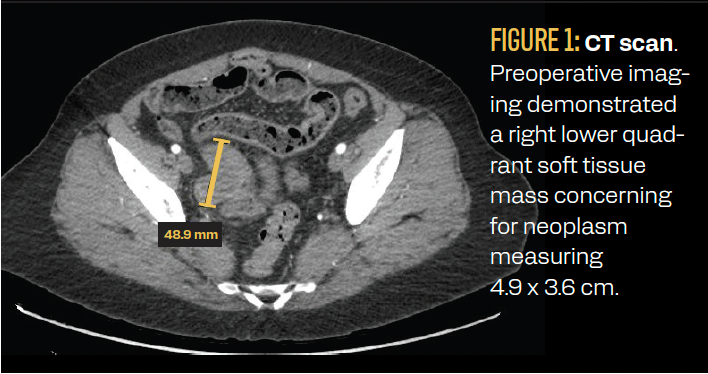

An initial CT scan of the abdomen and pelvis demonstrated a lobulated soft tissue mass in the right mid-pelvis likely originating from the distal ileum. The patient was referred to gastroenterology for a colonoscopy. Before the referral visit, the patient again presented to the emergency department with abdominal pain 1 month later. A repeat CT scan demonstrated a 4.9 × 3.6-cm right lower quadrant mass involving the distal ileum, with the potential for a neoplasm arising from the small bowel or within the right adnexa (Figure 1). A colonoscopy was performed and there was no mass noted in the distal ileum. The patient then underwent an exploratory laparotomy, extensive abdominal and pelvic lysis of adhesions, and a right colectomy with resection of the distal terminal ileum with primary anastomosis. An incidental solitary mesenteric implant was noted and was excised.

FIGURE 1: CT scan. Preoperative imaging demonstrated a right lower quadrant soft tissue mass concerning for neoplasm measuring 4.9 x 3.6 cm.